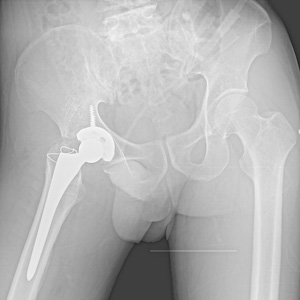

術(shù)后X片

把老邱所有的病歷整理后,王朝暉組織科室唐艷平、彭中財、何波涌、劉建偉、曾敏川、謝仙勇、吳石華及脊柱外科劉曉嵐博士等專家會診,每個人從自己專業(yè)方向一一把脈,針對老邱的病情闡述自己觀點及治療方案。討論的結(jié)果:老邱胸腰部僵硬,轉(zhuǎn)身困難,右側(cè)髖關(guān)節(jié)屈曲畸形、強直,活動喪失,由于長時間不能活動,右髖部的肌肉明顯萎縮,生活質(zhì)量極差,而且長期臥床及活動喪失已引起嚴重骨質(zhì)疏松,必須選擇適當位置截開,重建髖關(guān)節(jié)功能,手術(shù)難度極大。?

稍微停一下,王主任團隊討論分析后,一個清晰的方案呈現(xiàn)出來,果斷放棄常規(guī)大粗隆截骨,行前方部分截骨,既可滿意顯露以便股骨頸截骨,又盡可能減少對生理結(jié)構(gòu)的干擾,以利于術(shù)后穩(wěn)定及功能恢復。調(diào)整手術(shù)方案后,手術(shù)很順利,2個小時不到就完成了。